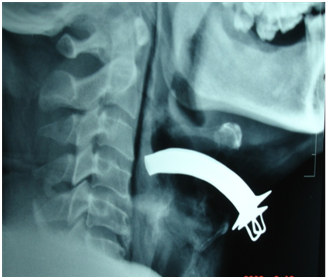

The second patient is a 58year male who came to the emergency room with alleged history of RTA following which he developed difficulty in swallowing and spitting out blood stained sputum. Examination revealed subcutaneous emphysema and tenderness over the laryngeal frame work. CT-neck plain showed extensive emphysema of neck with extension into the superior mediastinum (Figure 1) and fracture of thyroid cartilage at the midline with mild lateral displacement of the right side ala (Figure 2). He was admitted in the intensive care unit and was monitored for 24hours after which tracheostomy followed by neck exploration and laryngeal stabilization under general anesthesia was performed where in the fragmented thyroid cartilages were sutured. He was on ryles tube feed for 2months following which he was decannulated and ryles tube was removed.

Figure 1 X ray soft tissue neck lateral view revealed a defect in the thyrohyoid membrane.